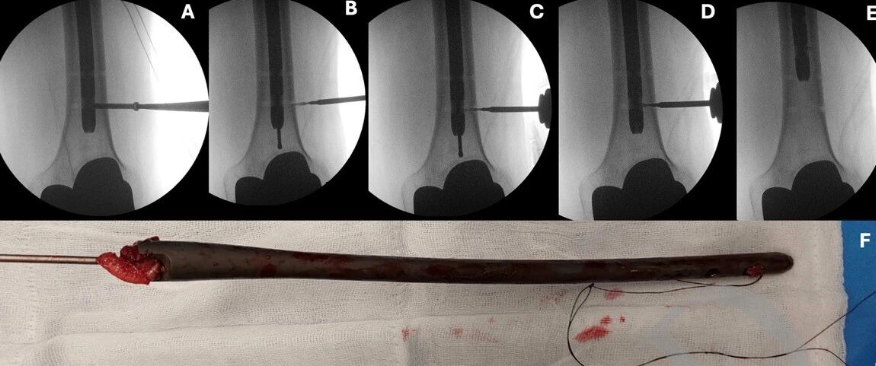

腓骨髓内钉固定减少一个切口可行吗?